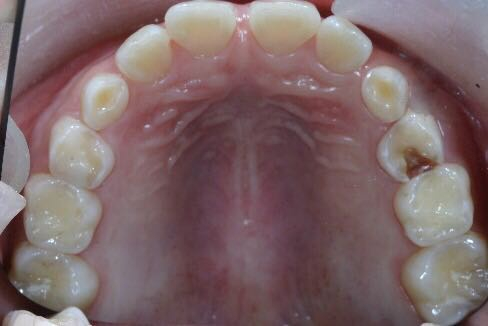

通过这些年的科普工作,“少吃糖,吃糖会蛀牙”几乎成了妇孺皆知的共识。然而,大众对于“糖”的认知还停留在非常浅的层面。在我们的门诊,询问病史的同时要了解孩子的饮食习惯,当问到孩子是 否经常吃甜食,喝饮料?往往得到的回答是否定的。糖会导致蛀牙,家长对其高度警惕,奶糖、巧克力几乎从来不给孩子吃;听说碳酸饮料很毁牙,也对孩子进行了严格控制。听起来孩子的饮食习惯似乎控制得不错,然而,面对孩子们一嘴的坏牙(图1),困惑的大夫决定好好“发掘”一下,结果发现孩子们每日的零食真是五花八门!除了睡觉,小嘴巴几乎就不闲着。曲奇、蛋糕这些甜点是小明的最爱 ;小花夏日未到,就一天吃好几次冰淇淋;球球的奶奶怕宝贝孙子“上火”咳嗽,每天早晨会给他熬上一锅冰糖雪梨汤;小可最喜欢吃柑、橙之类的水果,一天四五个都打不住,妈妈还经常给她榨橙汁喝……这样的例子多得不胜枚举,几乎每个有龋齿的孩子身上,都能发掘出一篇丰富多彩的“零食故事”。

图1 5岁儿童,多颗牙龋坏